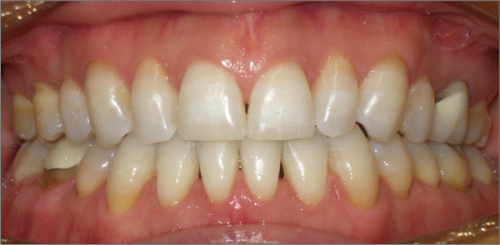

45 year old female:

Diagnosis:

- Missing upper left second bicuspid

- Lower arch crowding

- Edge to edge bite

Treatment:

- Extraction of upper & lower right second bicuspids

- Full fixed appliances

- 21 months